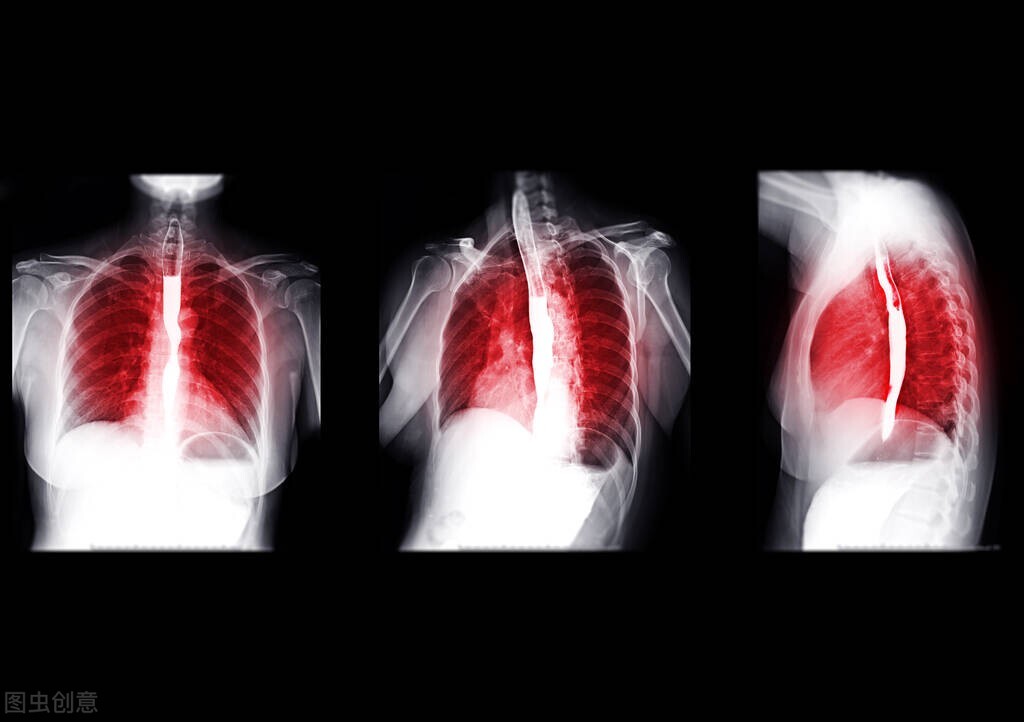

医生根据王老伯的描述为其安排了胃镜检查,发现食管中段有一2厘米左右的隆起病变,表面欠光滑,怀疑是恶性病变,又取了活检做病理检查,最后诊断为中分化鳞状细胞癌浸润。为进一步治疗,王老伯一家人来到了西京医院胸外科就诊。

最终,在完善各项检查后,考虑其可耐受手术,我为王老伯实施了腹腔镜下食管癌切除术+淋巴结清扫术,术后切除标本病理诊断为隆起型鳞癌,局部具有神经内分泌癌的部分特征,癌组织浸润至黏膜下层,脉管内查见癌栓,但食管切缘及周围淋巴结均未查见癌组织。